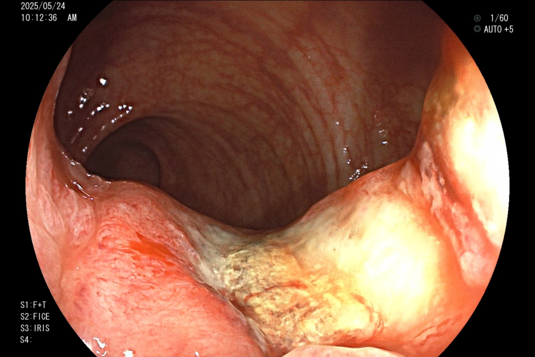

今年劳动节后,郑阿姨排便时总感觉疼痛,偶尔还发现便中带血。起初她没太在意,总想着“也许过几天就好了”。然而症状非但没缓解,反而逐渐加重。5月下旬,她终于来到昆山市中医医院肛肠科就诊。

直肠肿瘤

恶性可能性极大

在充分的术前准备后,一场腹腔镜下腹会联合直肠切除术(Miles术)紧张展开。